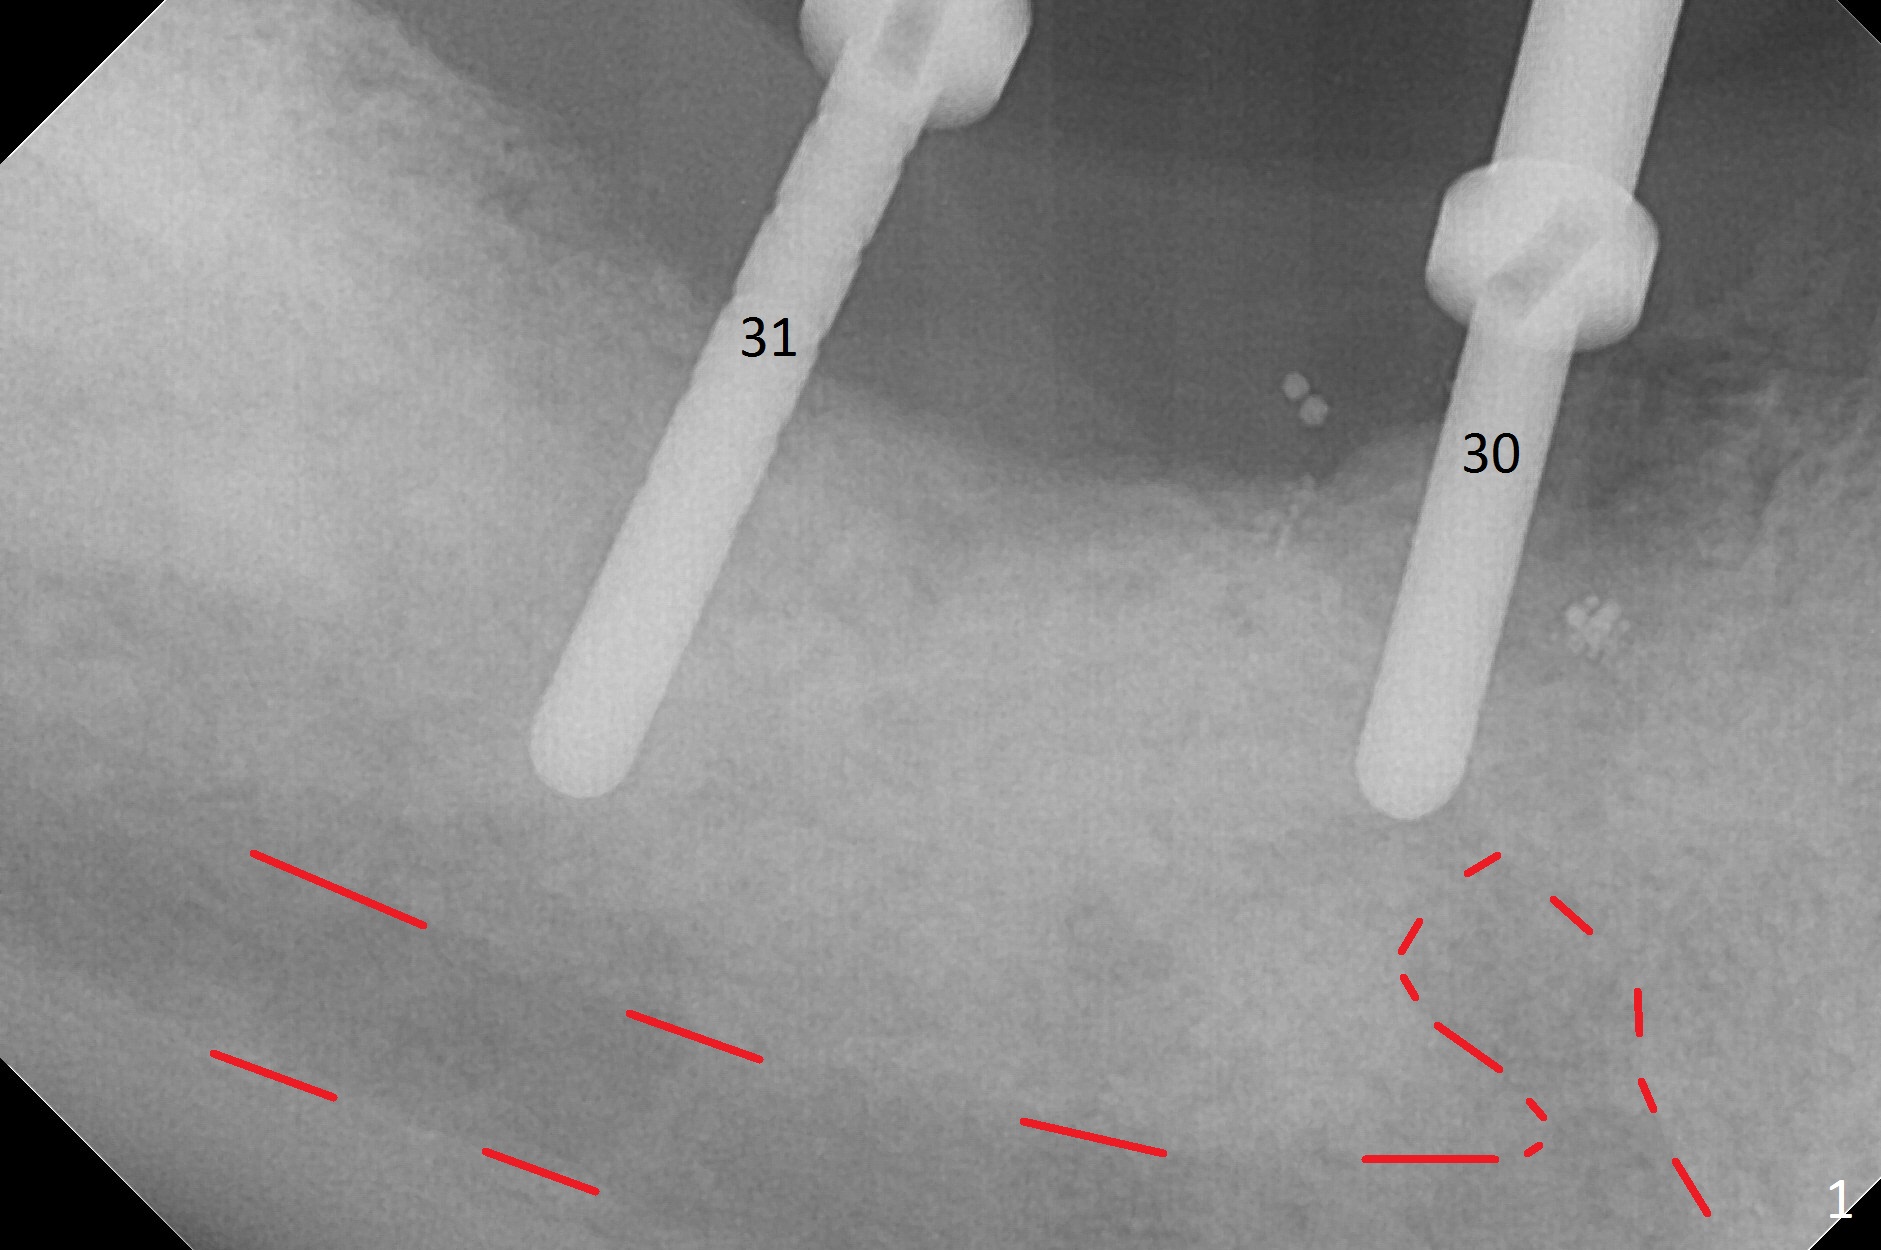

Initial osteotomy at #29-30 shows that there is clearance at #31, but not at #30 (Fig.1 (red dashed line: the superior border of the Inferior Alveolar Canal)) and that the osteotomy at #29 is close to the root of #28 (Fig.2). Moving the osteotomy of #29 distally using Lindamann bur is not sufficient (Fig.4 when a 3.8x10 mm drill is in place). A de novo osteotomy is established distally (Fig.5,6 (red dashed line: old osteotomy)).

At #31, the implant has to be placed low because of low buccal bone (Fig.8 B (vs. much higher lingual (L) one) in spite of 2 mm implant being coronal to the distal bone (Fig.3 ^). The margin of the abutment with 6 mm cuff appears apical to the distal crest (Fig.3 *). Bone graft is placed around the exposed implant threads (Fig.6 *) after placement of Osteogen plug between the implants (P). After placing PRF membrane (Fig.7 M) and plug (P) over the bone graft, Cytoplast (Fig.6,8 C: non-resorbable membrane) is used to assist wound closure. Finally periodontal dressing is applied for further wound protection (Fig.9).